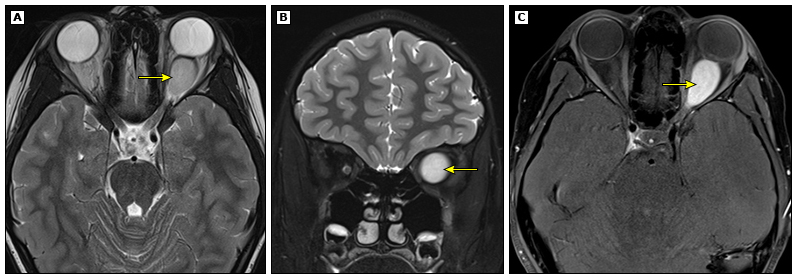

视路胶质瘤(15-20%患儿)可能导致视力下降,癫痫发生率约4-7%。